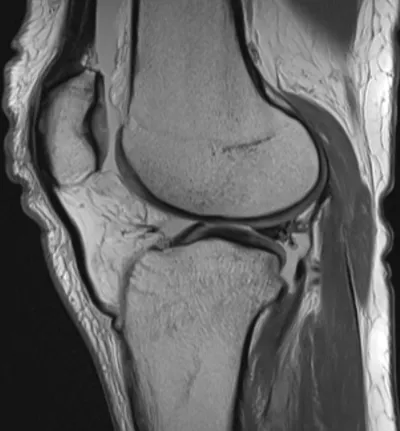

Meniscal Tear Radiology Images

Browse 4 medical images tagged with meniscal tear. This collection includes various imaging modalities for medical education and reference.

- This collection contains 4 radiology images related to meniscal tear, including various imaging modalities such as X-rays, MRIs, CT scans, and ultrasound images commonly used in medical diagnosis and education.